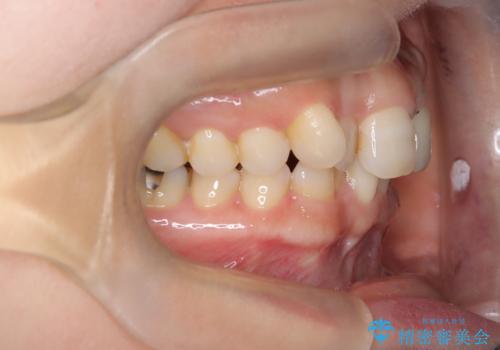

- 「八重歯をきれいにしたい」とのご希望で来院されました。診察の結果、上顎犬歯の萌出スペースが不足しており、典型的な八重歯(叢生)の状態でした。上下の歯の中心(正中)のずれや、奥歯のかみ合わせ(臼歯関係)のアンバランスも見られたため、単に見た目を整えるだけでなく、全体的な機能改善も必要と診断しました。

スペースを確保するために抜歯を行う選択肢もありましたが、歯列の幅や骨格とのバランスから判断し、上顎の奥歯を後方に移動させることでスペースを作る方針を立てました。そのため、まずリンガルアーチ(内側に装着する固定式装置)を用いて奥歯を遠心移動させ、その後ワイヤー矯正で歯列全体を整える治療計画を立案しました。